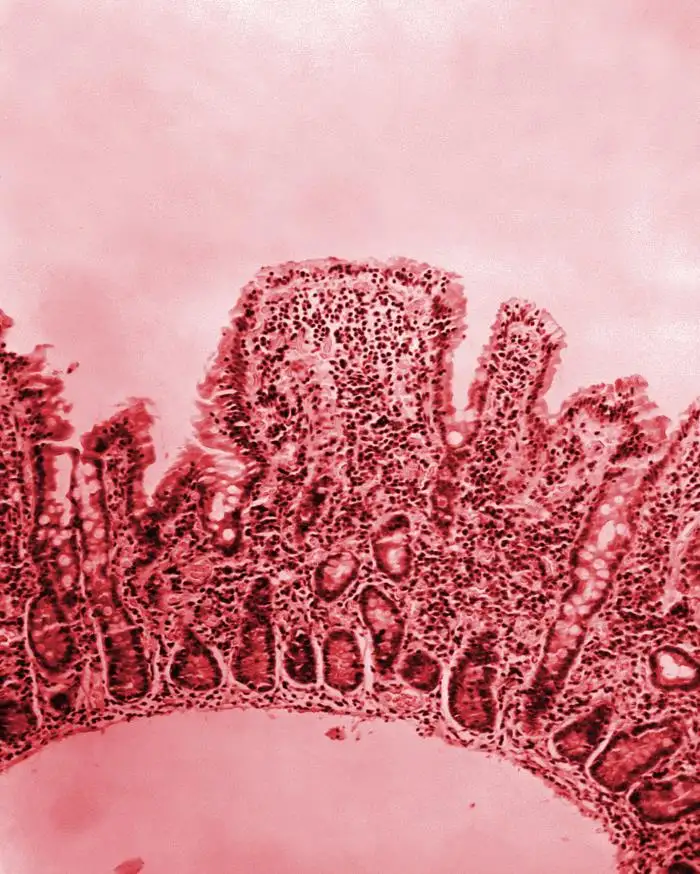

霍乱弧菌是一种极其狡猾的病原体。它的外形像一根微小的逗号,通常只有1.5到2微米长,0.5微米宽。在显微镜下,它们看起来像一群活泼的小鱼,依靠一根长长的鞭毛在液体中高速游动。当这种细菌通过污染的水或食物进入人体后,它们会在胃酸的屏障下损失大部分,但少数幸存者会进入小肠,那里温暖、潮湿、富含营养的环境为它们提供了理想的繁殖场所。在抵达小肠后的几小时内,这些细菌会迅速增殖,每二十分钟就能翻一番。一个霍乱患者在腹泻高峰期,每毫升肠液中可能含有超过一亿个细菌。

霍乱弧菌的致命武器是一种被称为"霍乱毒素"的蛋白质分子。这个分子量约为84,000道尔顿的蛋白质,是已知最有效的细菌毒素之一。它的结构异常精妙:一个A亚基负责产生毒性作用,五个B亚基负责与宿主细胞结合。当霍乱毒素进入小肠上皮细胞后,它会启动一系列连锁反应,最终导致细胞内的环磷酸腺苷水平急剧升高。这个看似简单的分子变化,却会产生灾难性的后果:小肠细胞会突然逆转它们的正常功能,不再从肠腔吸收水分和电解质,反而开始大量分泌液体进入肠道。一个严重感染的患者,每小时可能失去一升以上的体液。这些液体包含了大量的人体必需物质——钠、钾、氯、碳酸氢根离子——它们的流失会导致血液酸碱平衡崩溃、电解质紊乱、循环衰竭,最终导致死亡。

霍乱的致死机理几乎是完美的:它不直接破坏任何组织,不引起炎症反应,不入侵血液循环系统。它只是让患者的肠道变成一台失控的抽水机,将生命所需的液体源源不断地排出体外。患者死于极度脱水时,意识往往保持清醒,能够清晰地感受到自己的死亡过程。1829年,一位英国医生描述了一个典型的霍乱死亡病例:患者是一名为人开朗的年轻女子,在发病后十二小时内,她的皮肤变得如同干燥的羊皮纸,眼睛深陷,声音嘶哑如耳语。她一直保持清醒,不断哀求我们给她水喝。但即使我们满足她的请求,那些水也会在几分钟内被排出。她在极度干渴中死去,尽管她的床单已经完全湿透。

霍乱患者的典型症状——米汤样粪便——是这种疾病的标志性特征。这种液体呈现出一种浑浊的灰白色,像洗米水一样,带有淡淡的腥甜气味。它实际上是由脱落的上皮细胞、粘液和大量水分混合而成,几乎不含任何固体成分。一个严重病例在一天内可能排出多达十到二十升这样的液体。患者在发病初期往往会经历短暂的腹部不适和腹泻,但真正的恐怖始于大量体液的快速流失。在几小时内,患者会从外表完全正常变成一具"活着的干尸"——皮肤失去弹性,轻轻一捏就会保持皱褶状态;眼睛深陷眼眶,周围是一圈深紫色的阴影;手指和脚趾因严重脱水而呈现出独特的皱缩外观;声音嘶哑或完全失声。